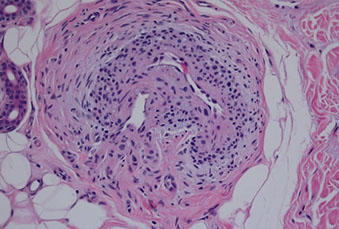

• Nodular vasculitis / Erythema Induratum (EI) of Bazin

Nodular vasculitis / Erythema Induratum (EI) of Bazin

Lobular panniculitis with vasculitis

- caseating necrosis or fibrosis possible

"Chicken soup" necrosis (often caseating) of fat lobule c MNGCs

- in septum may see nodular neutrophilic vasculitis

Erythema induratum